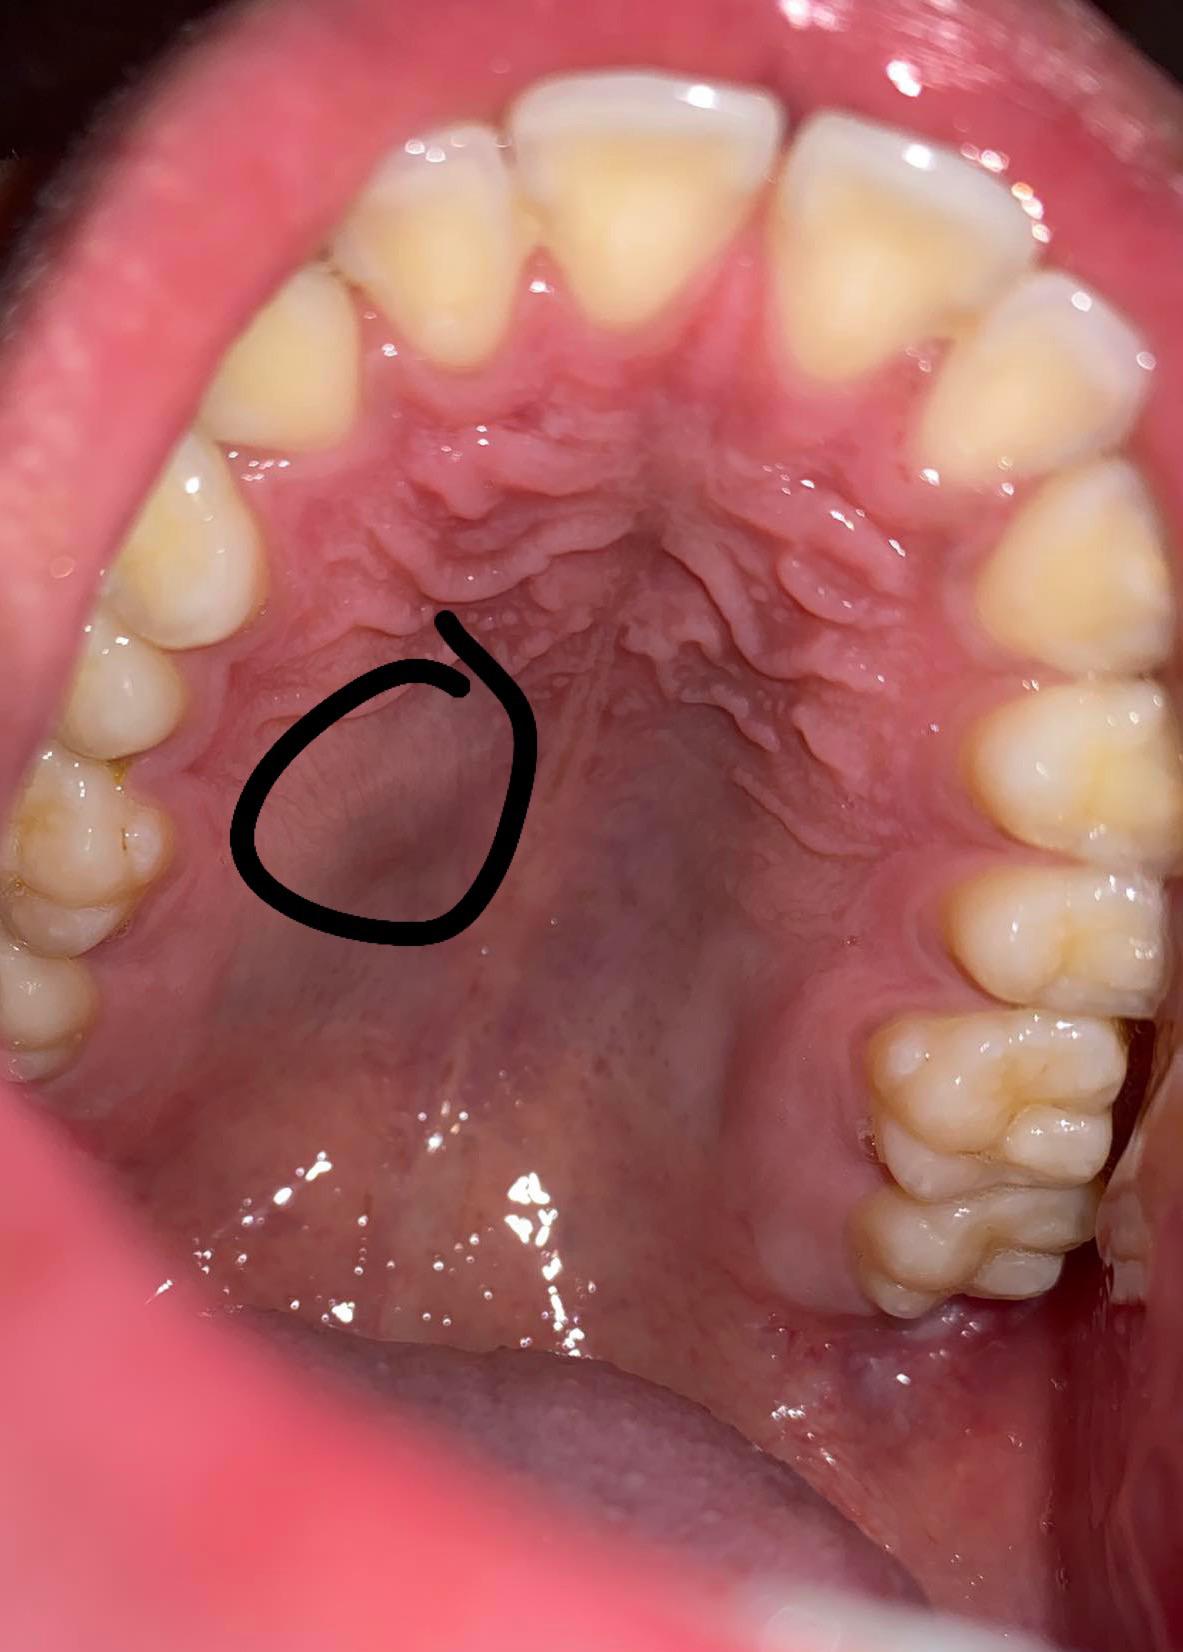

Lump on roof on mouth, I have a lump on the roof of my mouth, it’s painful to touch otherwise I ...

Discover the common causes of a nodule in roof of mouth. Learn when a hard bump or oral lesion requires professional dental evaluation. Understand potential triggers like palatal tori, cysts, or oral infections, and identify symptoms that warrant a visit to your dentist for a proper diagnosis and effective treatment plan for your oral health.

TitleLump on roof on mouth, I have a lump on the roof of my mouth, it’s painful to touch otherwise I ...